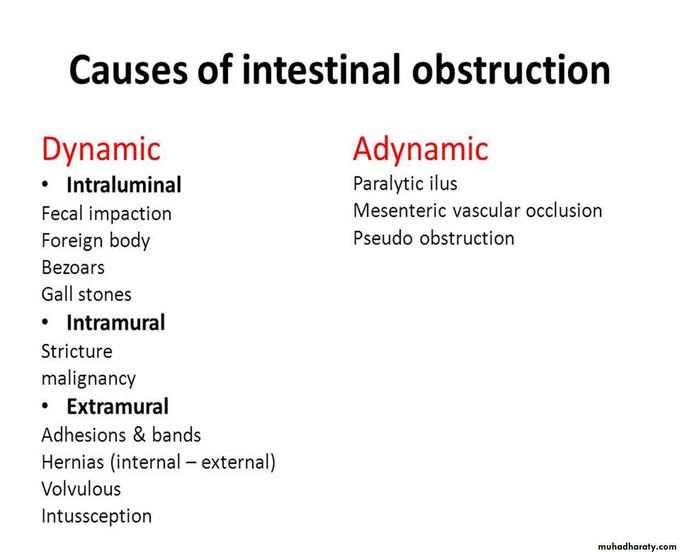

Bowel Obstruction Causes

Intestinal Obstruction

Intestinal Obstruction

Intestinal Obstruction

Intestinal Obstruction Presentation And Treatment